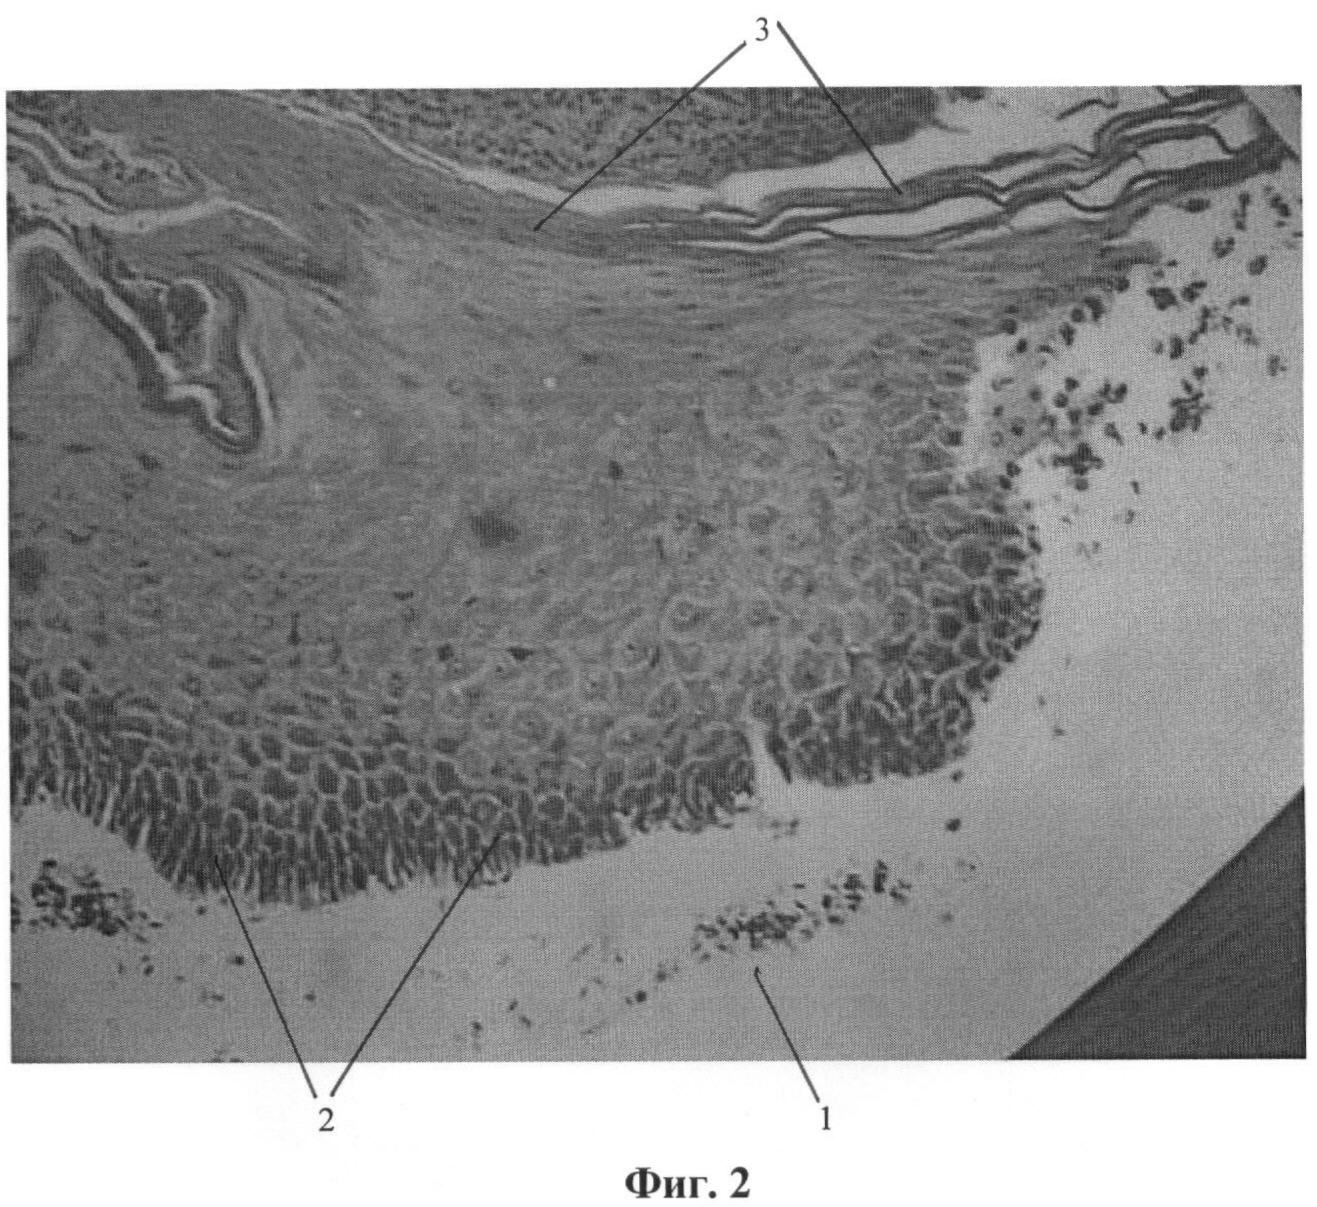

Это подтверждается фотографиями гистологических препаратов, где на фиг.1 (при увеличении ×800) представлен поперечный срез участка раневой поверхности на третьи сутки лечения с помощью предлагаемого способа, на фиг.2 (при увеличении ×400) – поперечный срез участка раневой поверхности на третьи сутки лечения с помощью пленочного покрытия («Биокол – пленка» по примеру 1), на фиг.3 (при увеличении ×400) – поперечный срез участка раневой поверхности на третьи сутки лечения с помощью гелевого покрытия («Биокол – гель» по примеру 1). Препараты окрашены традиционно по методике Гематоксилин – Эозин («Практическая микротехника и гистохимия», Д. Кисели, Будапешт, 1962, стр.115).

Как видно на фиг.1, на раневой поверхности 1 наблюдается быстрый горизонтальный рост базальных эпидермоцитов 2 в 1-2 слоя клеток, в то же время при использовании только пленочного (фиг.2) или только гелевого (фиг.3) покрытия на раневой поверхности 1 наблюдается бурный вертикальный рост эпидермоцитов 2 с быстрой его дифференцировкой и кератинизацией 3.

Более медленное закрытие раны при вертикальном росте эпидермоцитов может привести к избыточному росту фибробластов и образованию рубцов.